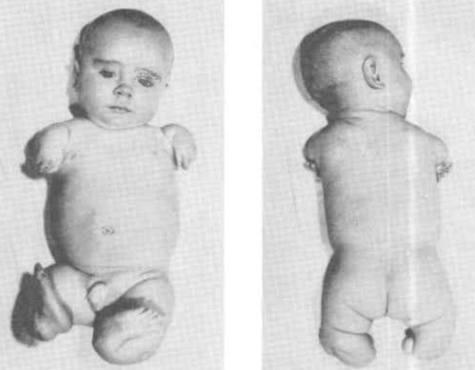

What is Prune Belly Syndrome?

Rare congenital abnormality. A partial or complete lack of abdominal wall muscles w/ renal abnormalities. Usually in males.

anterior abdominal wall defect

urinary tract obstruction

cryptorchidism

hypoplastic abdominal wall muscles

massive distention of bladder

wrinkling

urethral obstruction

bladder enlarges

mega ureter

hydronephrosis

abdomen enlarges

abdominal muscles becomes abnormal

Babies are delived c-section

Prune Belly

Prune Belly

What is another name for prune belly syndrome?

Eagle Barrett syndrome

What is the sonographic appearance of prune belly syndrome

hydronephrosis with echogenic renal parenchyma

oligohydramnios

urinary ascites

a dystrophic bladder

peritoneal calcifications